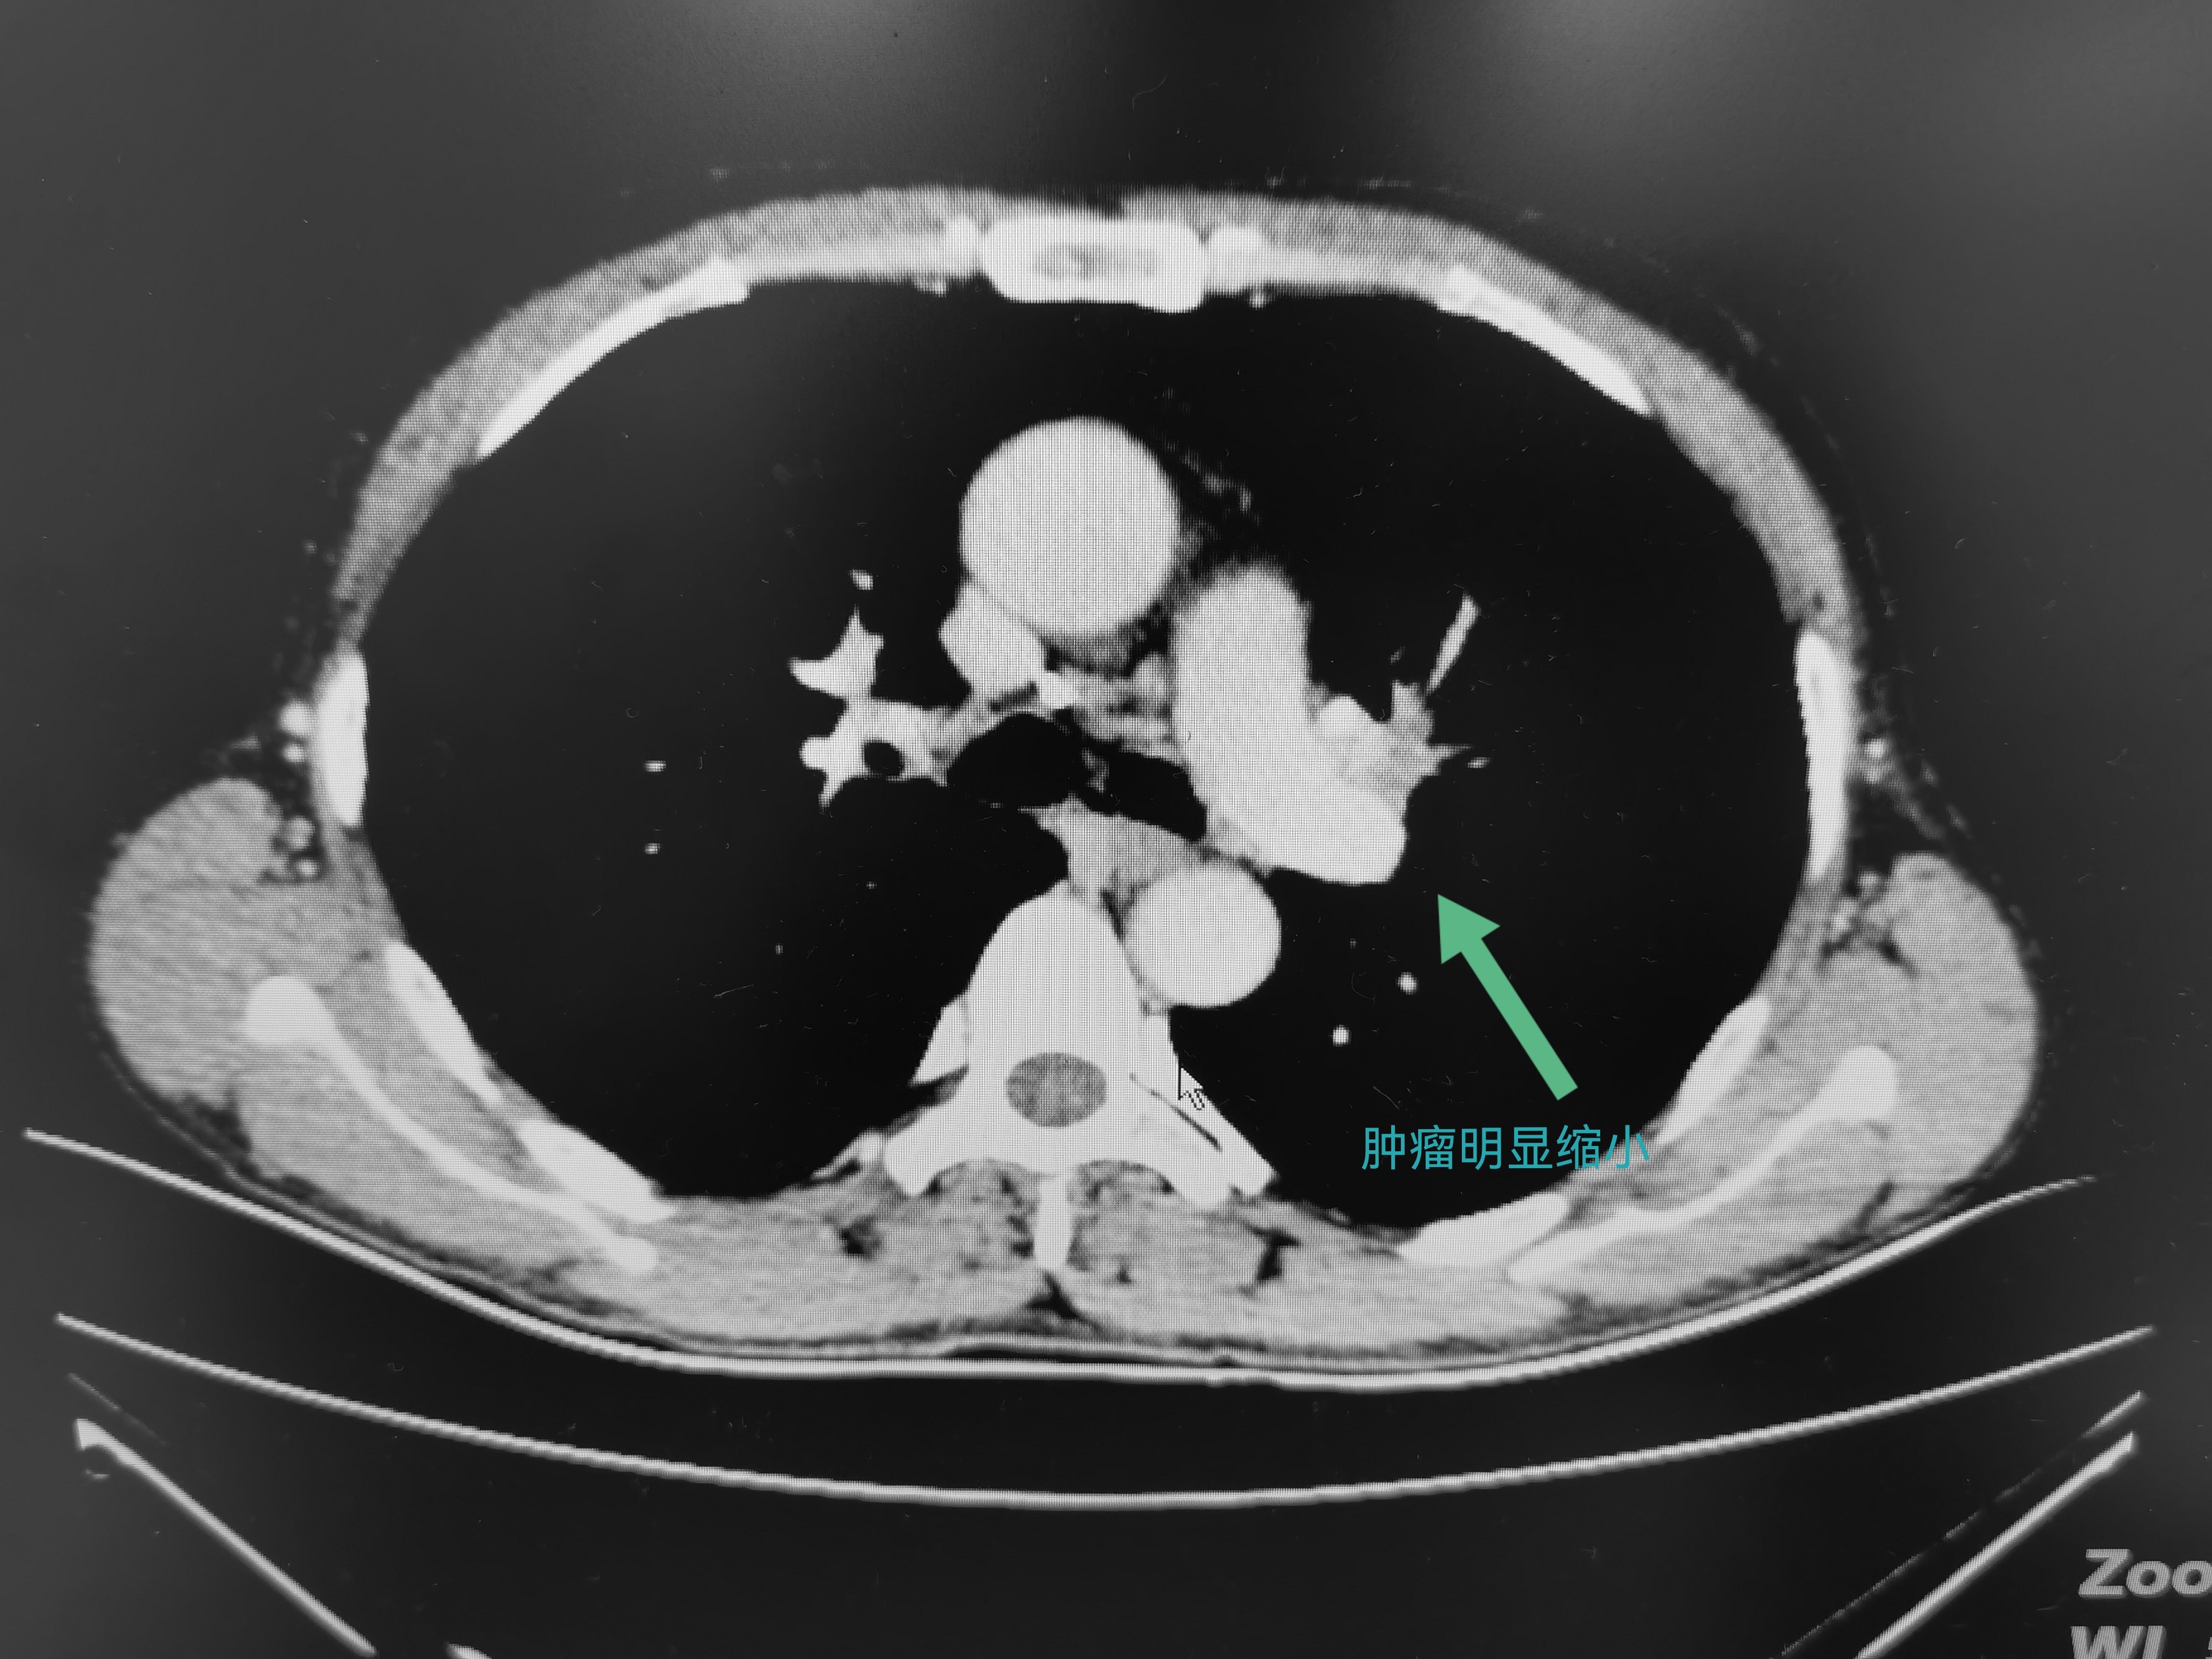

因为咳痰带血,65岁的刘爷爷来到成都市第三人民医院普胸外科就诊。“医生,快点帮我看下是啥问题,我还赶着回家收花生呢。”对于自己的病情,没有其他不适感的刘爷爷很乐观,认为“问题绝对不大”。然而,检查结果却很糟糕——左肺肺门区长了一个直径约4.5cm的肿瘤,并且肿瘤已经侵犯到肺动脉主干和支气管,经过病理检查证实为肺鳞癌。唯一说得上幸运的是,没有发现远处脏器有转移灶。

尽管如此,想要直接手术切除的风险很大,可能无法达到根治性切除的目的。也可能需要切除整个左肺,而这必将对老人家后续的生活造成巨大的影响,大幅降低生活质量。经过“肺癌一体化诊疗中心”多学科团队的讨论,最终根据患者的实际病情制定了个体化的治疗策略——结合目前指南推荐和各种大型研究的结果,决定先行三周期的免疫联合化疗,目的是先“杀灭”一部分潜在的微转移灶和肿瘤细胞,同时使肿瘤变小,以获取小范围根治性切除的机会。

在新辅助治疗顺利结束复查时,刘爷爷的肿瘤已经缩小至2cm。这意味着,可以通过手术完整切除病变的左肺上叶,同时保留左肺下叶,以最大限度保障后续生活的质量。

新辅助治疗前

新辅助治疗后